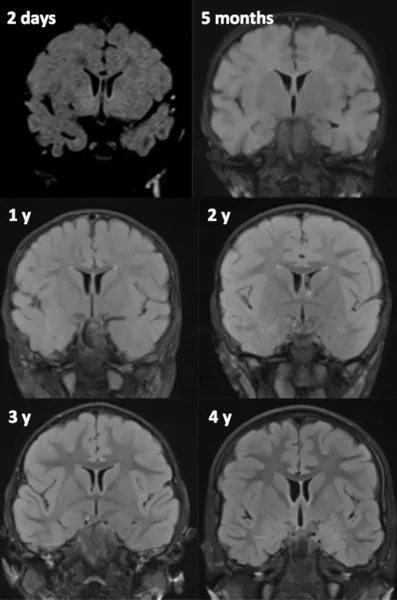

MRI Techniques

In neonates and young infants (Girard et al., 2007, 2012; Girard and Raybaud, 2011) the standard MRI protocol consists of axial and coronal T2-weighted images (WI), sagittal and axial gradient echo T1 WI, axial diffusion or diffusion tensor images, and proton spectroscopy. In older infants and children axial T2, coronal fluid-attenuated inversion recovery (FLAIR) and three-dimensional T1 WI are the common standard anatomic sequences. T1 WIs are generally acquired using gradient echo, spin echo, or inversion recovery (IR) images. GE and IR T1 WI allow excellent grayâwhite-matter differentiation, especially in young infants less than 6 months of age. Alternates for T1 WI consist of three-dimensional (3D) T1 images whenever possible. T2 WI can be acquired using spin echo, fast spin echo (FSE), or turbo spin echo (TSE) techniques. FSE and TSE images show myelin maturation at an earlier age than spin echo images due to increased magnetization transfer effects (Welker and Patton, 2012) and are obtained in a shorter acquisition time. Heavily T2-weighted sequences are used in infants less than 12 months of age to compensate for the long T1 values due to the increased cerebral water content (Girard et al., 1991). In older children a FLAIR sequence is also performed. Although FLAIR images are considered highly efficient in assessing the white matter, these images demonstrate a paradoxic signal pattern through infancy: in neonates the white matter is of low signal intensity as on T1 WI, then of high signal intensity in infants and young children, and reaches the mature aspect of low signal intensity as on T2 WI around 4 years of age (Fig. 57.1).